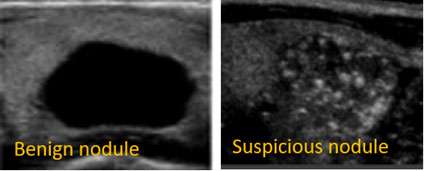

Not all thyroid nodules need a biopsy. For many thyroid nodules we see in our office, we choose not to biopsy because the ultrasound appearance is so reassuring. That is one way to avoid over treatment. For example, nodules that appear completely black on the inside (“anechoic”) are purely cystic, or filled with fluid. The chance of thyroid cancer for a cystic nodule is essentially zero and cystic nodules do not require biopsy. There are guidelines from the American Thyroid Association that will help your doctor determine which nodules to biopsy based on their size and how suspicious they look on the ultrasound.

There are certain factors that make a nodule suspicious for thyroid cancer. For example, nodules that do not have smooth borders or have little bright white spots (micro-calcifications) on the ultrasound would make your doctor suspicious that there is a thyroid cancer present. If the nodule appears suspicious on ultrasound and is larger than 1cm, the next step is to do a thyroid biopsy.